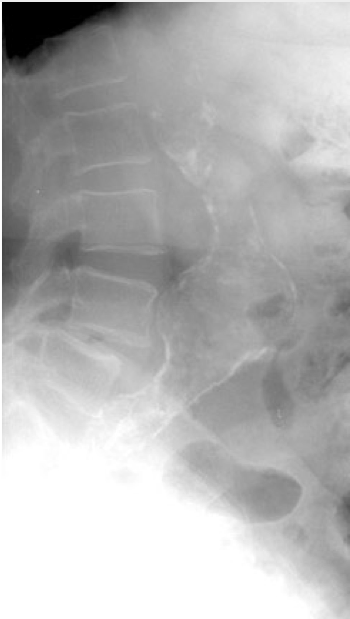

If a patient with a known history of AAA arrives unstable with symptoms consistent with rupture, no confirmatory diagnostic tests are necessary and the patient should be transferred to the OR expeditiously. Most patients, however, will require bedside imaging to confirm the diagnosis. Bedside ultrasound has emerged as the test of choice in this case. Ultrasound has a sensitivity of 98% in fasted patients undergoing screening, and while bowel gas and body habitus can hinder the exam, this is less of an issue in imaging the larger aneurysms that are likely to present ruptured. To obtain images of the aorta, a low frequency curvilinear probe is used. The probe is placed in the midline in the high epigastrium, and, using the liver as an acoustic window, gentle steady pressure is applied to displace bowel until the spine is visualized. The aorta will be seen as a round, hypoechoic structure on the patient’s left. (Figure 2) The sonographer should attempt to scan throughout the length of the aorta to the bifurcation (typically at the umbilicus), and should also obtain a sagittal view. Importantly, the diameter is measured from outer wall to outer wall, with > 3.0 cm being abnormal. If ultrasound is not available, a cross table lateral X-ray may show an AAA in up to 67% of cases. (Figure 3)

Figure 3: A lateral abdominal X-ray showing the classic eggshell calcification of a AAA, confirming the diagnosis with 100% specificity. Image obtained from Radvany MG, Cho KJ. Abdominal Aortic Aneurysm Imaging. Retrieved from: http://emedicine.medscape.com/article